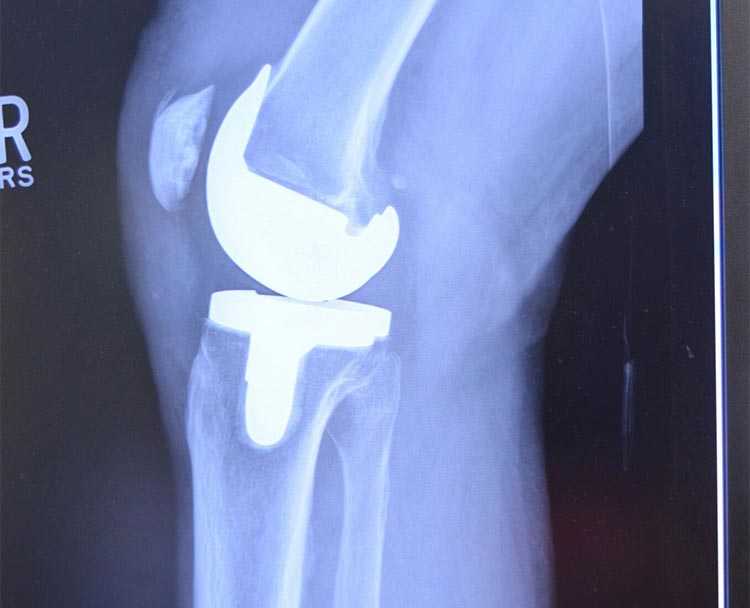

One of the most common causes of knee pain and loss of mobility is the wearing away of the joint’s cartilage lining. When this happens, the bones rub against each other, causing significant pain and swelling.